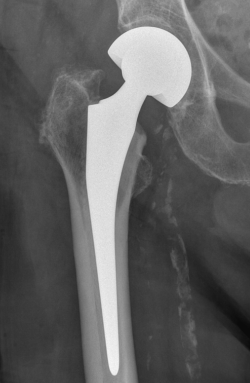

Ursache für komplexe Knochenbrüche wie Hüft- oder Schulterfraktur ist eine reduzierte Knochenqualität. Die häufigsten dieser Verletzungen sind die handgelenknahe Speichenfraktur (Radiusfraktur), die hüftgelenknahe Oberschenkelfraktur (mediale/pertrochantäre Fraktur), die Schulterfraktur (proximale Humerusfraktur) oder die Fraktur eines oder mehrerer Wirbelkörper.

Diese Verletzungen können für einen älteren Menschen teilweise gravierende Folgen haben. Eine Schenkelhalsfraktur kann bei einem älteren Patienten mit dem plötzlichen Verlust seiner Selbstständigkeit und Mobilität verbunden sein und eine Vielzahl anderer Komplikationen nach sich ziehen. Eine drohende temporäre oder dauerhafte Pflegebedürftigkeit kann sich daraus entwickeln.